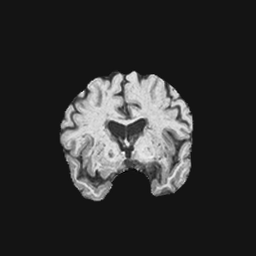

Exp. 2: Fetal brain data is used to test the robustness of our approach under real conditions. Fetuses younger than 30 weeks very often move a lot during examination. Fast MRI sequences allow artifact free acquisition of individual slices but motion between slices corrupts consistent 3D information. Fig. 3 shows that our method is able to accurately predict also under these conditions. For this experiment we use from three orthogonally overlapping stacks of ssFSE slices covering the fetal brain with approximately 20-30 slices each. We are ignoring the stack transformations relative to the scanner and treat each individually. For , 28 clinically approved motion compensated brain reconstructions are resampled into a volume with spacing. A density of 500 unique sampling normals has been chosen via the Fibonacci sphere sampling method with 25 sampling planes evenly spaced between -25 to +25 on the Z-axis. This gives a plane spacing of 2mm, sampling only the middle portion of the fetal brain. Training took approximately 10hrs for 30 epochs. Prediction, i.e., the forward pass through the network, takes approx. 12 ms/slice.

0..5 Randomly selected illustrative inference results

Here we show for Exp. 1, Exp. 2, and Exp. 3 randomly selected examples of images that have been presented to the network (ground truth) compared to an image sampled at the predicted location.

In these experiments, we present a ground truth (GT) image to the network to estimate the respective transformation parameters needed to reorient the slice in its correct world co-ordinates. Using the transformation parameters, we generated a slice from the 3D atlas in the location where the network has predicted that slice should be (denoted as SVRNet).

The slices are compared side-by-side to give a visual representation of “where the slice really is” and “where the network thinks the slice is”.

0..5.2 Exp. 2:

Slices, from a motion corrupted MRI stack, are segmented and cropped. Since there is no ground truth for the queried images, an arbitrary fetal atlas is used for visualization in Fig. 11 and 12.